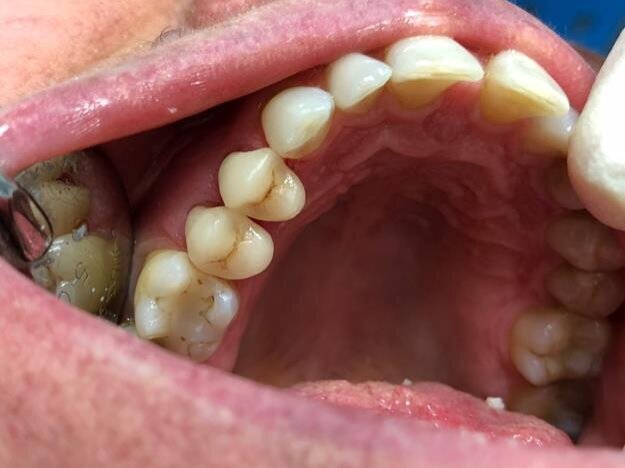

Fig. 7: Final result from side

After performing the silanization process inside the crowns, the cementation was done once again using Relyx Unicem. The crowns seem to be perfectly coinciding and integrating with the surrounding teeth, totally closing the margins previously prepared. Therefore, no occlusal retouching was done. The patient left our clinic satisfied with the precision, the little time spent and the aesthetic result.